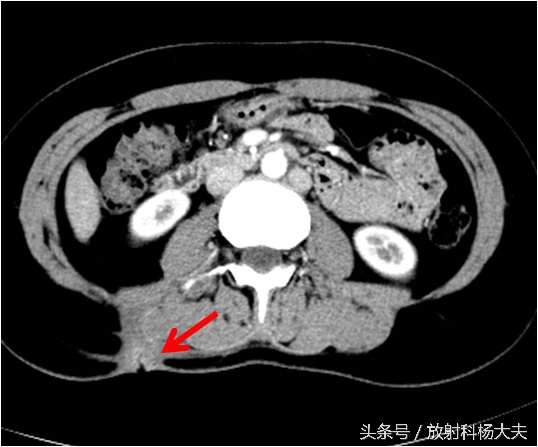

骨科接着开了腰椎CT,骨科大夫怀疑背部是一个窦道,猜测窦道可能是脊柱旁,因此开了腰椎CT平扫,腰椎CT扫描的时候是以腰椎和椎间盘为主的,范围不大,但我们却在不大的范围内发现了问题,除了窦道,肾上有东西!但腰椎CT平扫实在难以评价,因此做了腹部增强CT,发现了实属罕见的情况:那个确实是个窦道,如下图红箭所示,窦道外口在体表,也就是流水的地方。窦道的上口却是在肾脏!